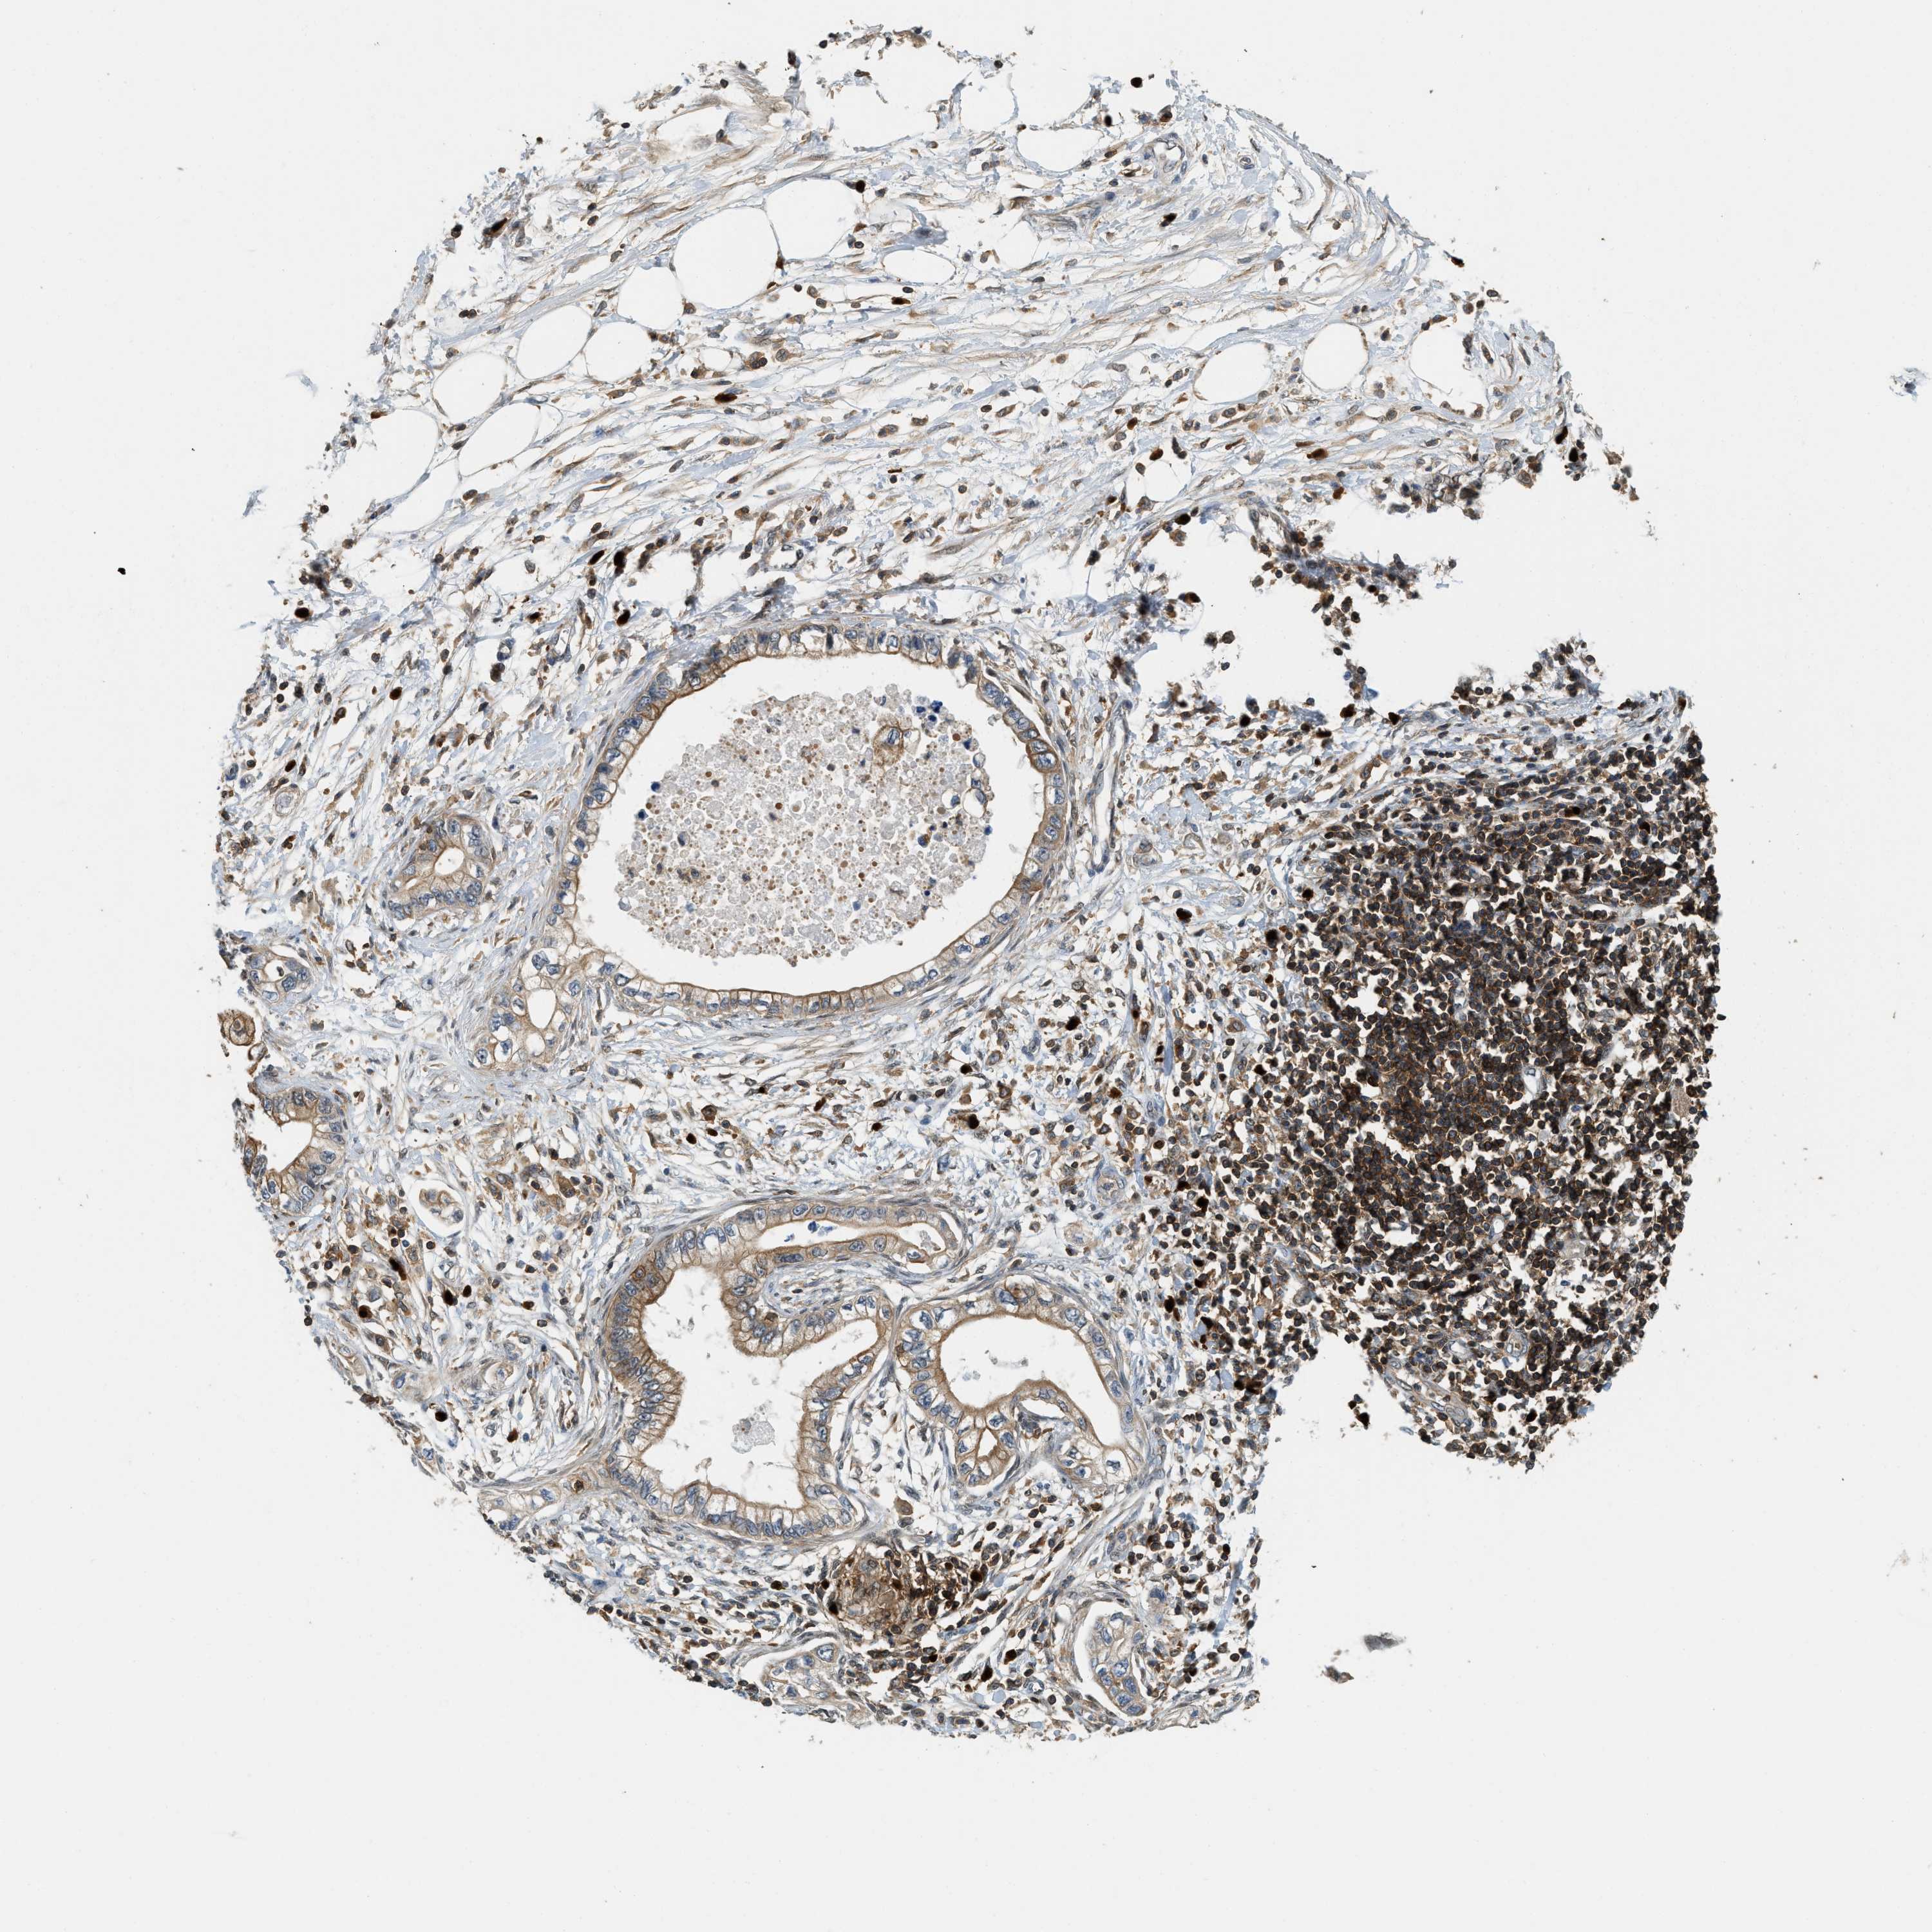

PANCREATIC CANCER - Protein expressioni

A mouse-over function shows sample information and annotation data. Click on an image to view it in a full screen mode. Samples can be filtered based on level of antibody staining by selecting one or several of the following categories: high, medium, low and not detected. The assay and annotation is described here.

Note that samples used for immunohistochemistry by the Human Protein Atlas do not correspond to samples in the TCGA dataset.

Antibody stainingi

Antibody staining in the annotated cell types in the current human tissue is reported as not detected, low, medium, or high, based on conventional immunohistochemistry profiling in selected tissues. This score is based on the combination of the staining intensity and fraction of stained cells.

Each image is clickable and will lead to virtual microscopy that enables deeper exploration of all samples and also displays staining intensity scores, fraction scores and subcellular localization as well as patient and tissue information for each sample.

Antibody HPA014657

Staining

High

Medium

Low

Not detected

Intensity

Strong

Moderate

Weak

Negative

Quantity

>75%

75%-25%

<25%

None

Location

Nuclear

Cytoplasmic/membranous

Cytoplasmic/membranous,nuclear

Adenocarcinoma, NOS